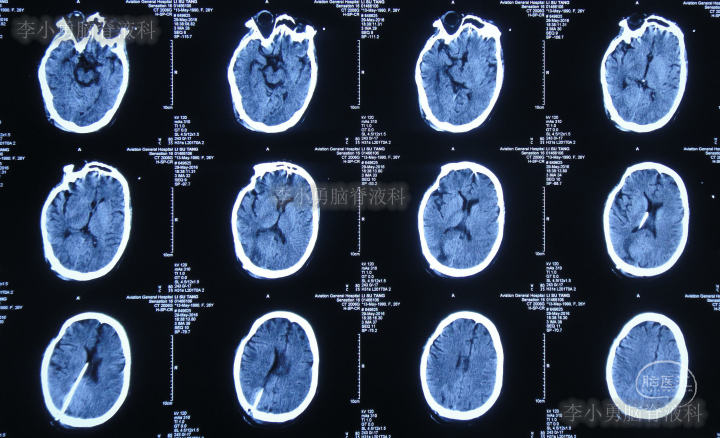

第三家医院第3次门诊图-1

图-1:2016年3月18日头颅CT